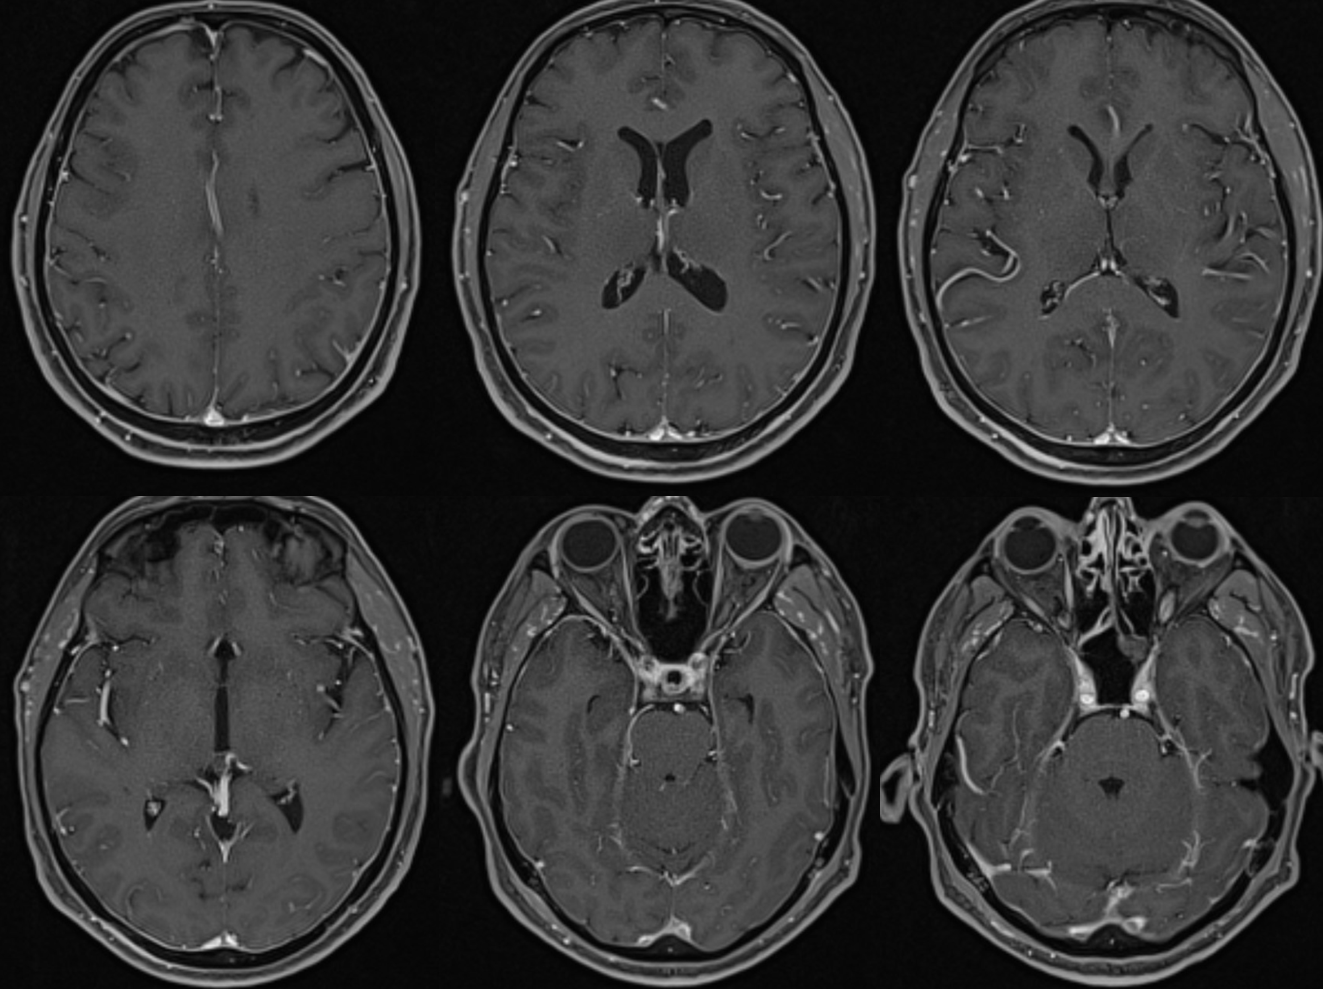

All of the above anatomic knowledge can become very useful in evaluation of venous thrombosis. Numerous collateral pathways develop in this setting attempting to compensate for the loss. The most dramatic cases usually involve the largest channel — the superior sagittal sinus. In this case, a man presented with what initially was thought to be vasculitis-related brain hemorrhage. Subsequent workup led to an angiogram, where sagittal sinus thrombosis with extensive trans-cerebral and trans-osseous emissary vein collateral channels was seen. In retrospect, these findings were present on the patient’s earlier contrast MRI. “Venovibe” or other contrast-enhanced MR venograms can very sensitive, particularly when interpreted with the appropriate index of suspicion. Noncontrast 2-D time of flight MRV I consider to be next to useless as a problem-solving technique. Any thin-slice postcontrast T1 study is vastly superior.